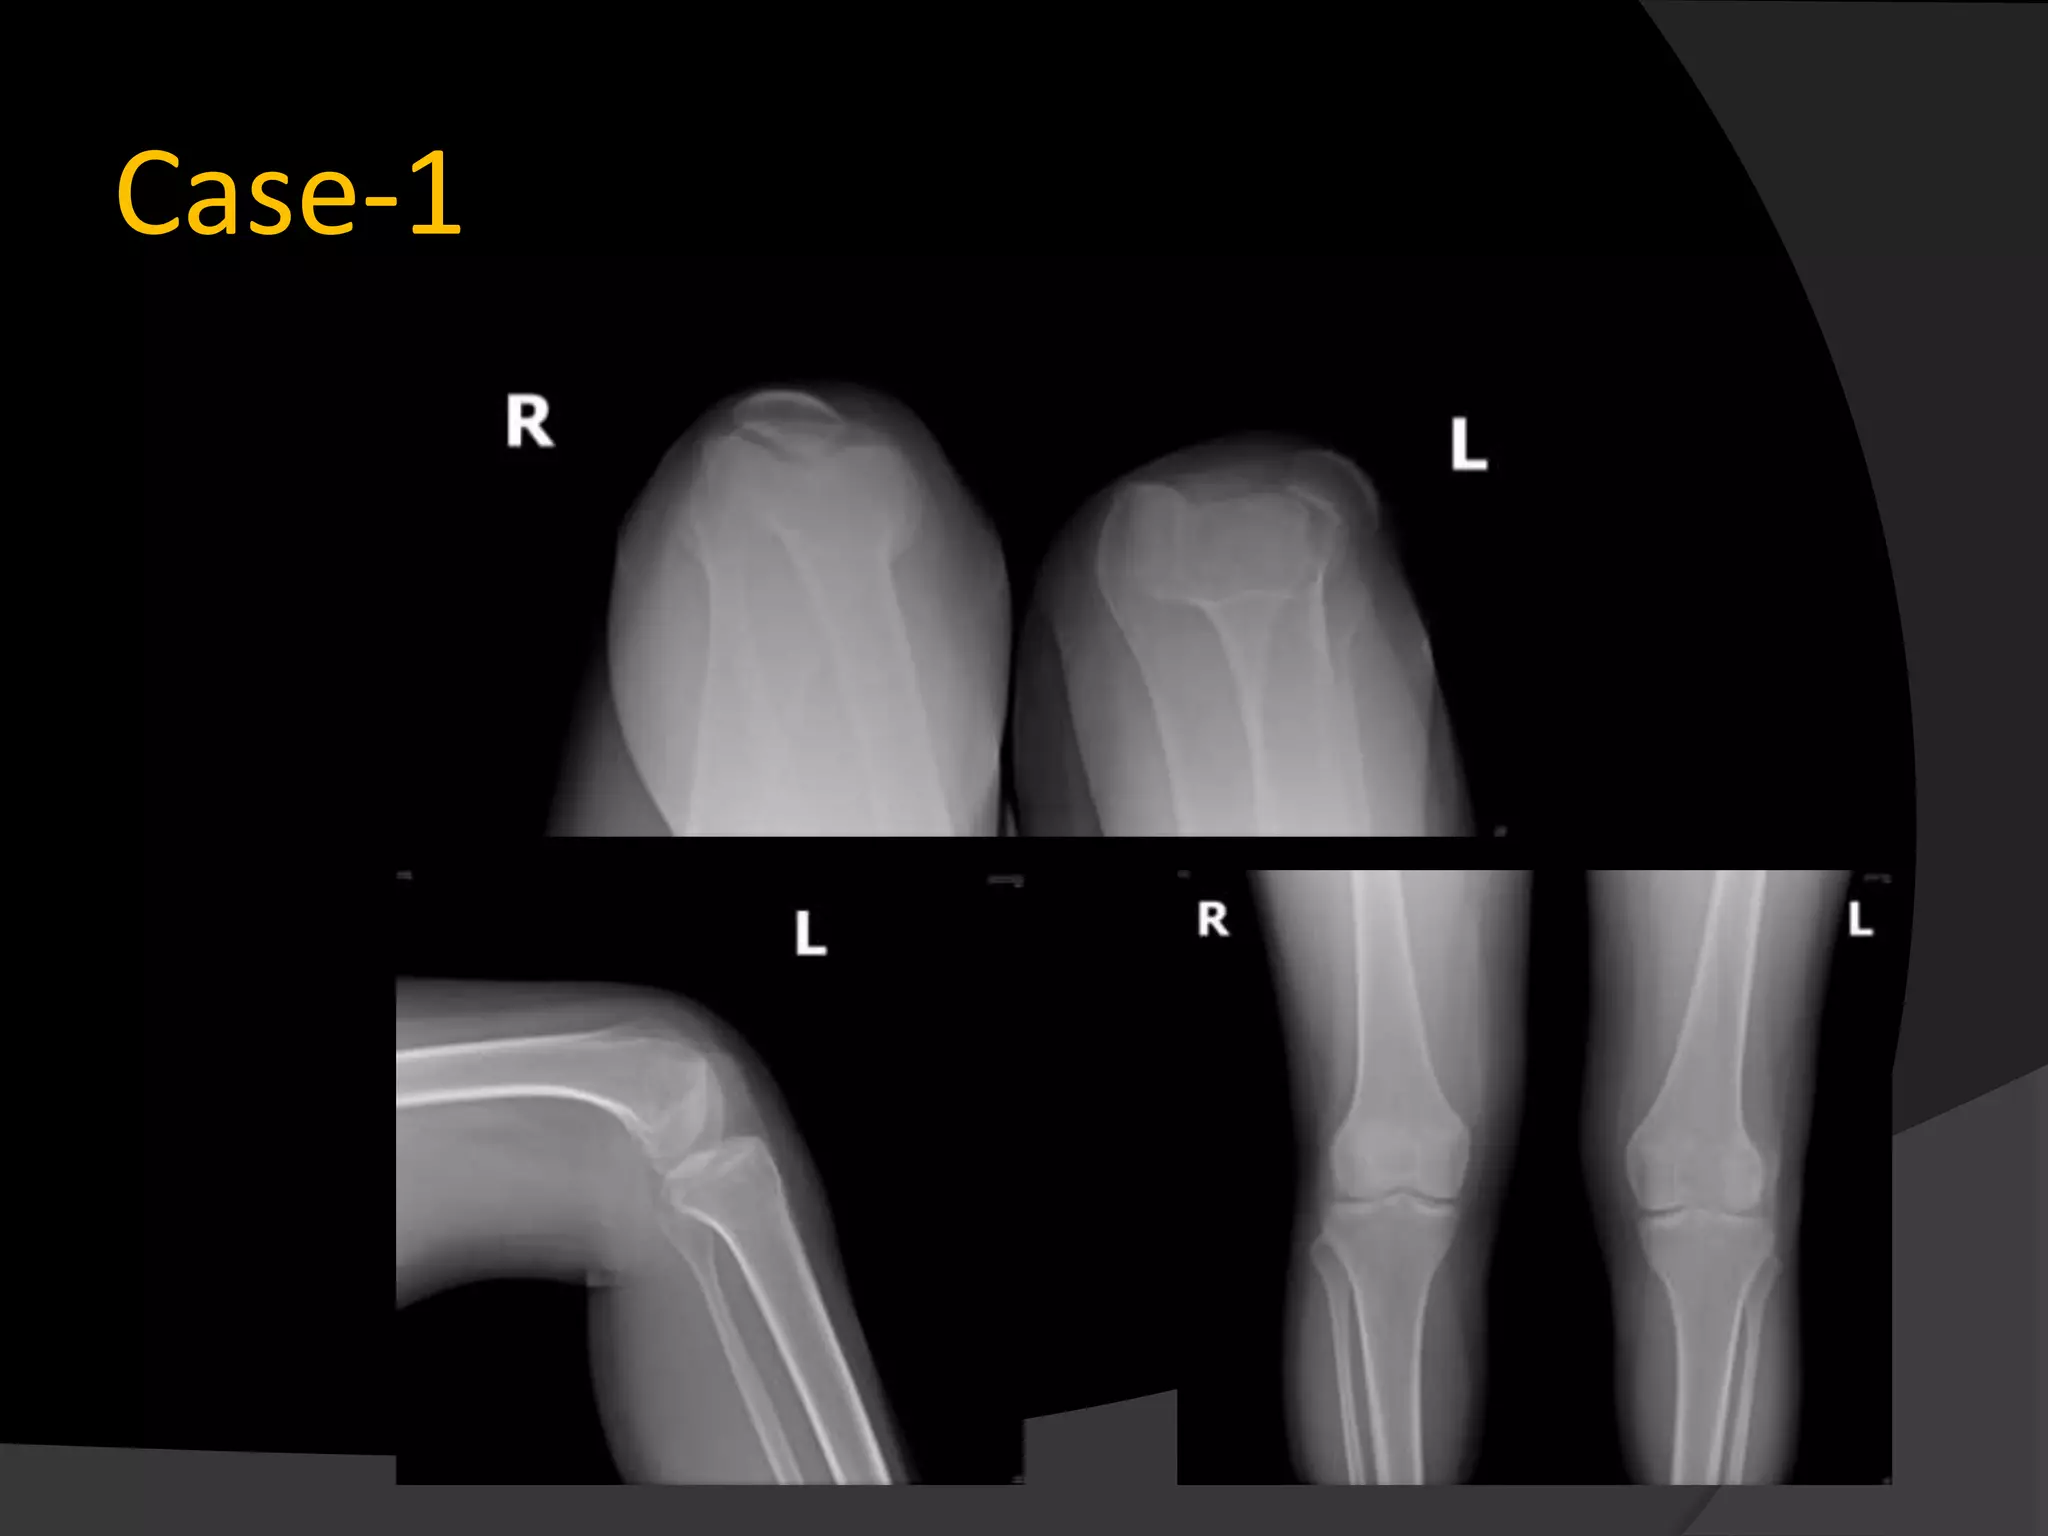

Case-1

Material and methods 14 Patients with patellar instability were enrolled in this study from 2008-2012 5 habitual dislocation 9 Recurrent dislocation Medial patellofemoral ligament pathology was confirmed by both clinical and radiological examination. Apprension test was positive in 12 patients Average Q angle..